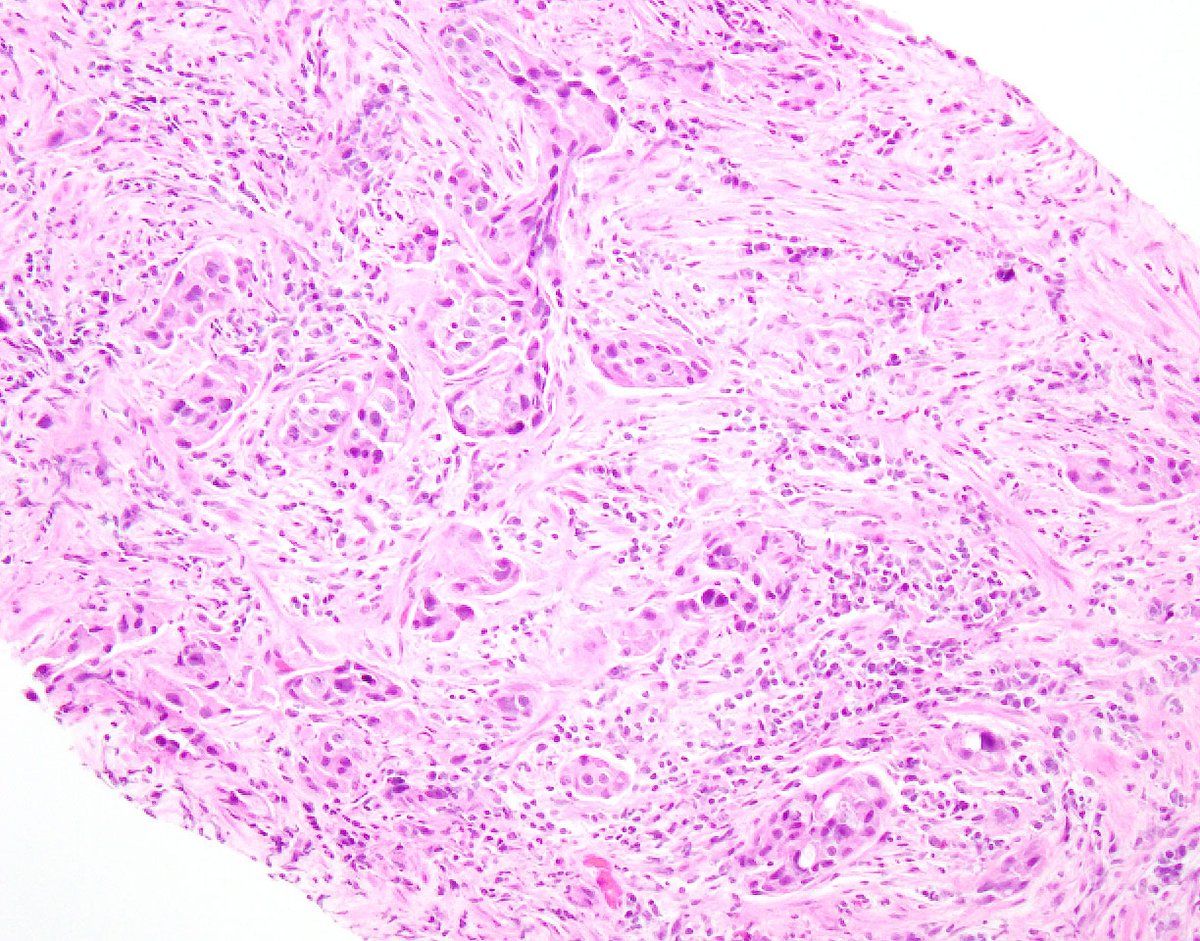

Rare diagnostic pitfall Bladder mass in a 70yo male. Epithelioid cells with focal spindle cell morphology and atypical mitoses, marked variation in nuclear size and shape, hyperchromatic, occasional intranuclear inclusion. Note the absence of in situ carcinoma. see next tweet.

This is a case of metastatic melanoma to bladder. This mass was black in cystoscopy. Less than a 30 are reported in the literature, but the true prevalence is higher, autopsy series on melanoma patients reported 3-18% prevalence. M : F = 15 : 8. #gupath #pathology #bladdercancer